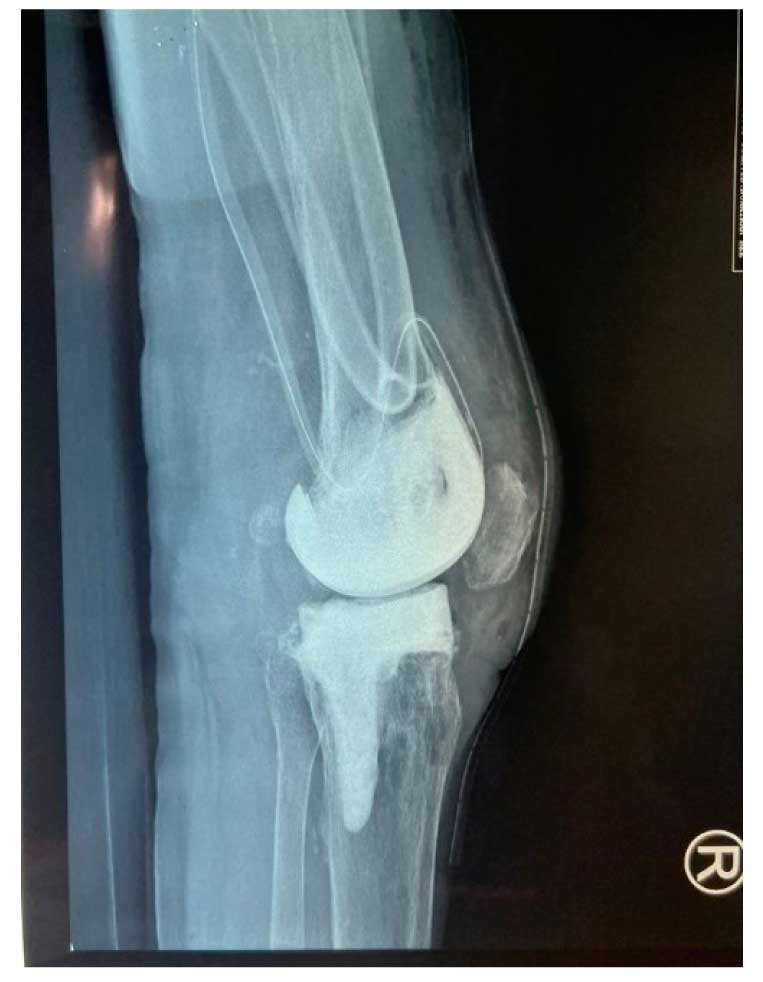

Case report: This study reports a case of prosthetic joint infection in a patient who had a previous history of total knee replacement surgery. Cy. fabianii was recovered from intraoperative culture specimens identified by matrix-assisted laser desorption/ionization time-of-flight mass spectrometry and confirmed using molecular assays. It was, however, initially misidentified as Candida utilis by phenotypic identification.